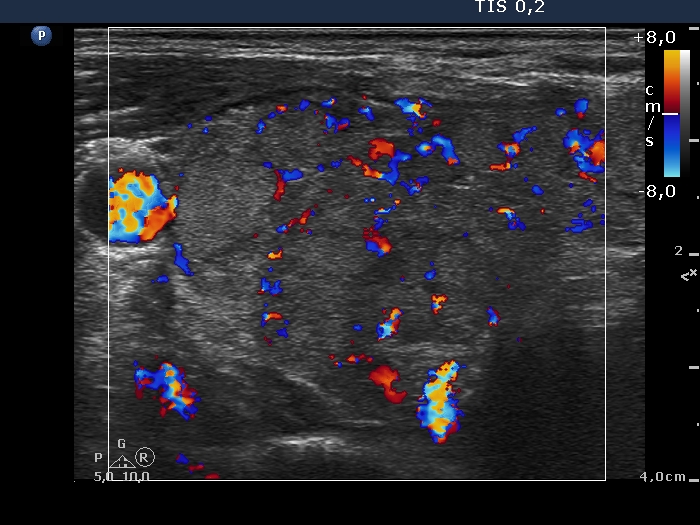

Lymphocytic thyroiditis - case 609 (ultrasonographic picture 4)

Right lobe, transverse scan, color Doppler mode.